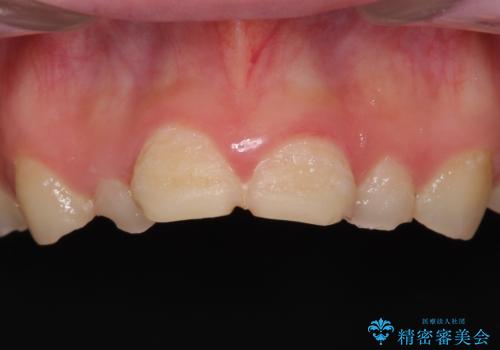

- 一時期の拒食症に伴い歯が酸で溶けてボロボロになってしまったとのことで来院された患者様です。

酸によりエナメル質の大半が溶けており、下顎前歯以外は酷いむし歯のような状態でした。